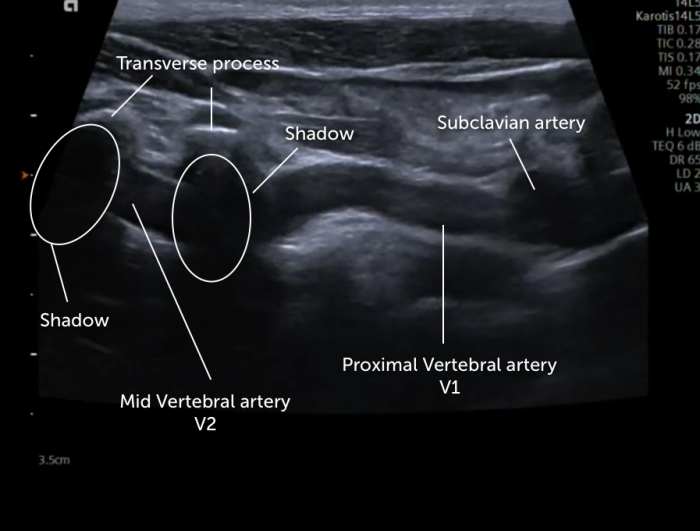

경동맥 초음파는 목 양쪽의 경동맥(carotid artery)에 초음파 탐촉자를 대고 혈관 벽 두께(IMT), 혈류 속도, 협착(좁아짐) 여부를 실시간으로 관찰하는 비침습적 영상 검사입니다.

- 누운 자세 유지 – 목을 15° 가량 뒤로 젖혀 검사사가 좌·우 경동맥, 추골동맥까지 스캔합니다.

- 즉시 결과 상담 – 촬영 영상을 보며 의사가 협착률·IMT·혈류 속도(Vmax, PSV, EDV)를 설명합니다.